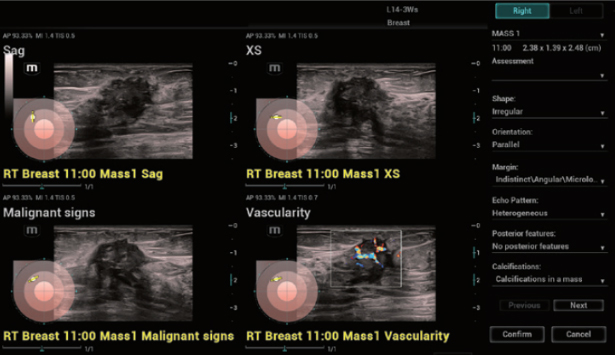

Zaawansowana diagnostyka